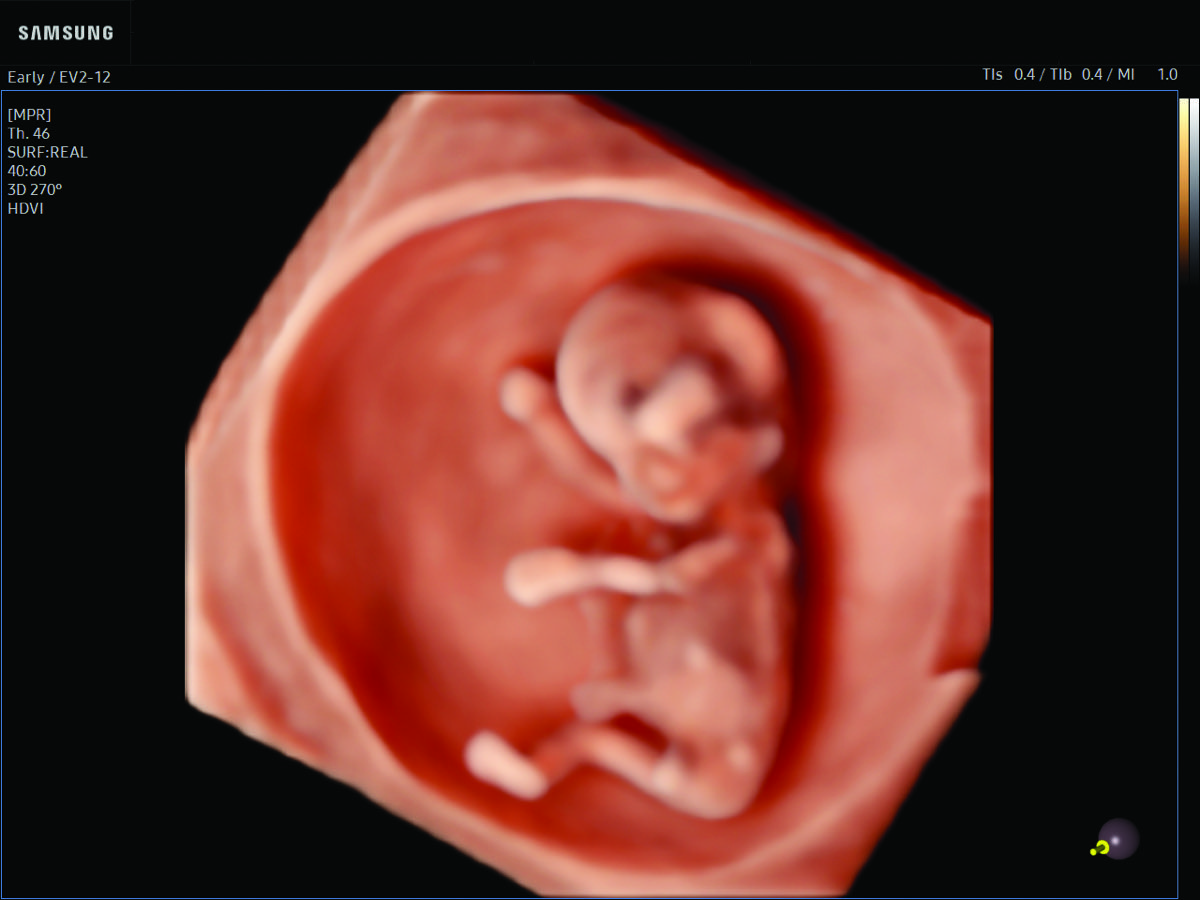

Comprehensive, advanced and expert MFM care for high-risk pregnancies

- Fetal anomalies